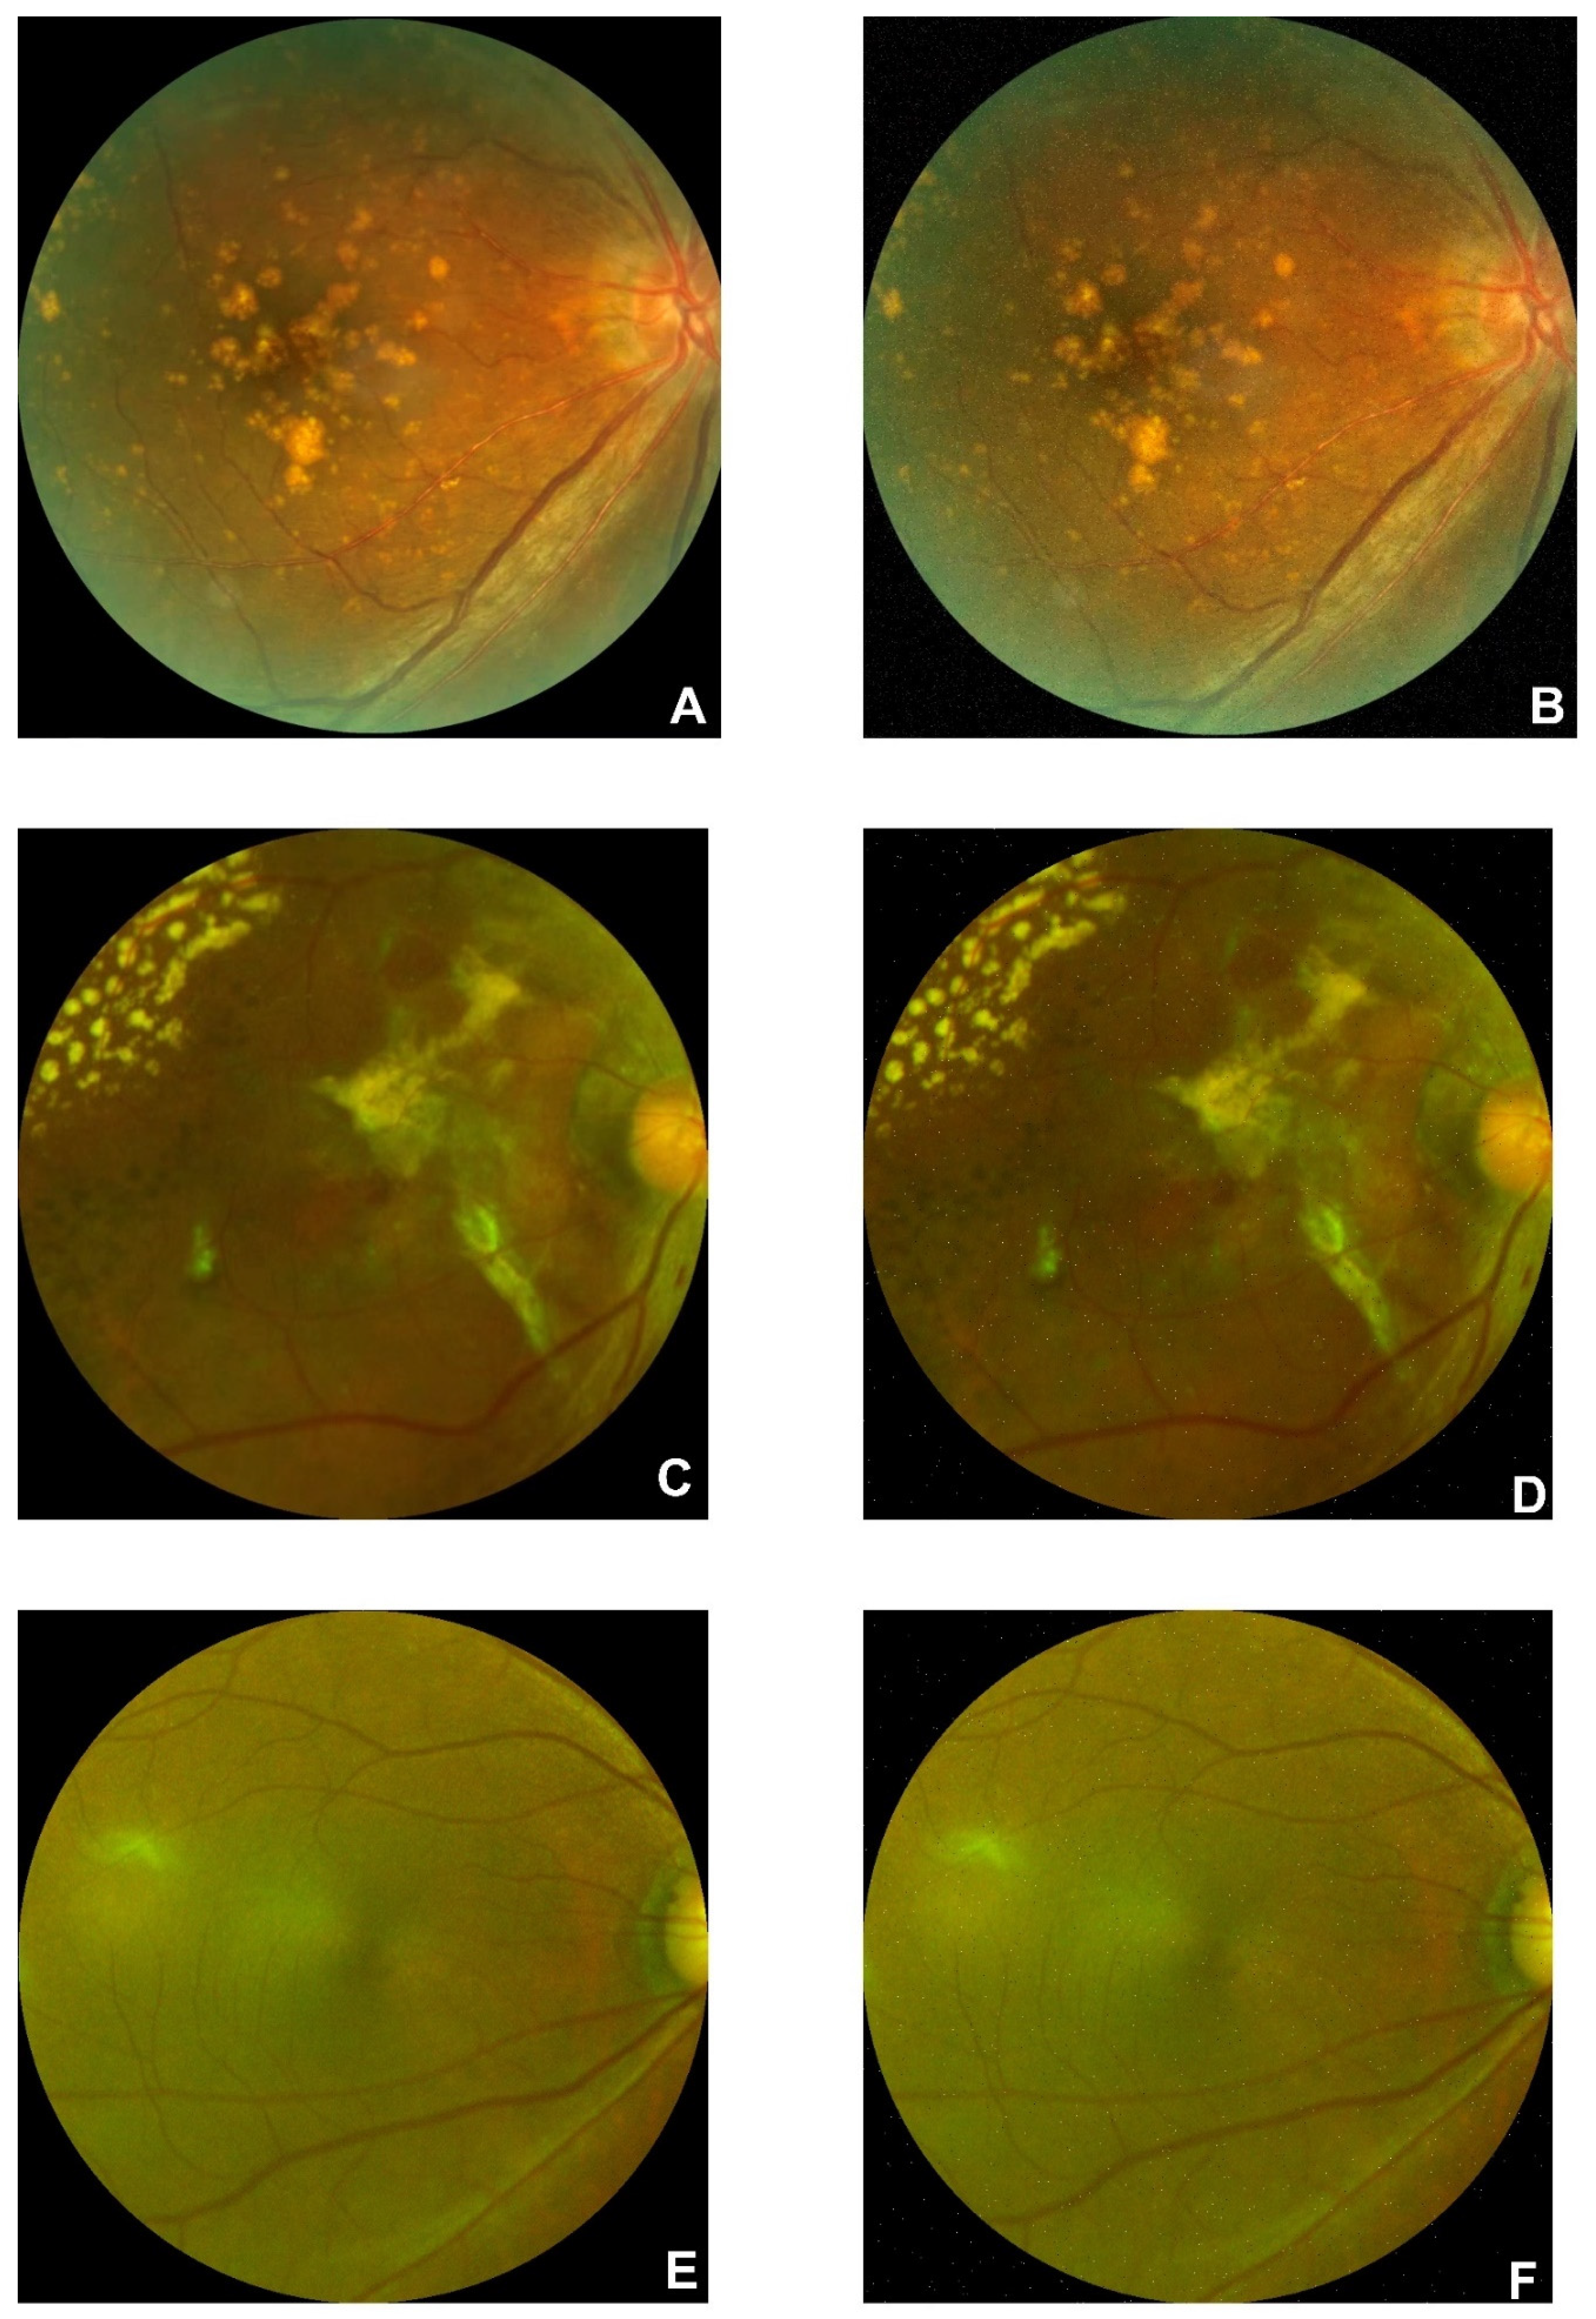

There are 1947 AMD and 2874 normal images in the FAF dataset. Examples of AMD (A, B, and C) and normal (D, E, and F) are illustrated in

Figure 2. Drusen and CNV emerged in AMD images. According to the former research, there is a 0.083-21.69% reported rate of adverse reactions, and the rate of deaths is 1:100,000 to 1:220,000[

54]. Furthermore, rotating is performed on the dataset to enhance the size of the dataset.

Figure 2.

Original figures of FAF images. Subfigures of D, E, and F are related to normal subjects. Subfigures of A, B, and C are related to the AMD subjects with choroidal neovascularization symptoms.